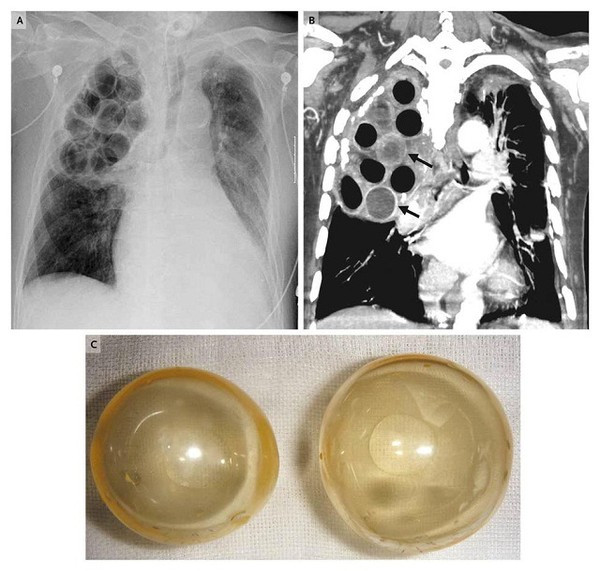

Đây là một biện pháp điều trị đầy mạo hiểm được sử dụng vào những năm đầu thế kỷ XX cho các bệnh nhân lao. Cụ thể, các bác sĩ sẽ tiến hành phẫu thuật với hai bước chính. Đầu tiên họ sẽ "đục" những lỗ nhỏ trong phổi bệnh nhân, rồi trám vào đó những… trái bóng nhựa.

151112med04-12a42

Theo lý thuyết vào thời này, các trái bóng nhựa sẽ giúp phần phổi bị nhiễm trùng tự lành trở lại. Tuy nhiên, đây chắc chắn là một phương pháp phản khoa học, vì chỉ có thuốc mới có thể diệt được khuẩn tuberculosis gây ra bệnh lao mà thôi.

151112med05-a4e70

Sau một khoảng thời gian áp dụng không hiệu quả, phương pháp này dần bị loại bỏ ở phần lớn các nước phát triển.